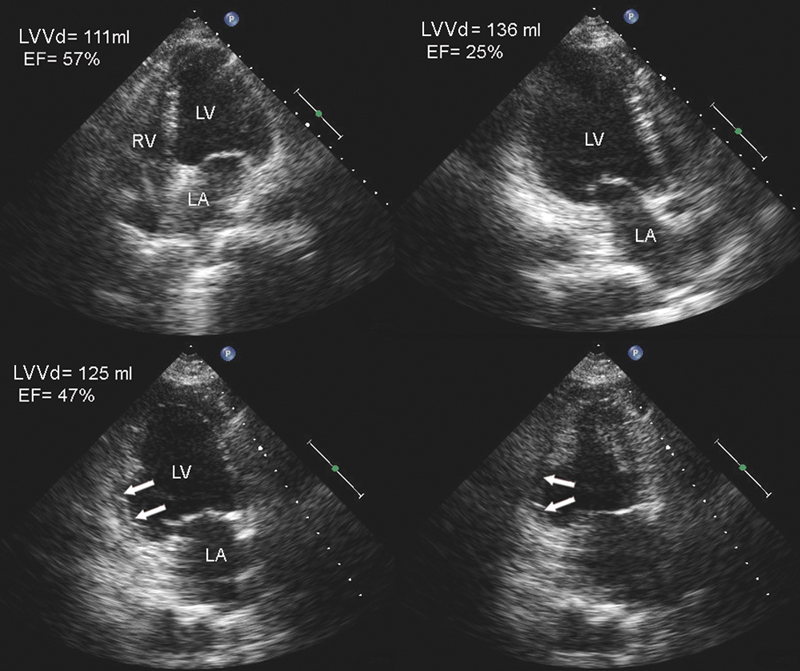

فحوصات تشخيصية لبعض امراض القلب والشرايين التاجية